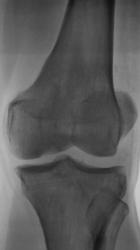

Пациент, врачом хирургом, направлен на рентгенографию коленного сустава в связи с болями. Пациент отмечает, что боли ощущает в течение уже 2-х лет. Ранее производилась рентгенография коленного сустава, однако патологических изменений выявлено не было.

А травмы не было? Латеральнее ММВ как будто бы фрагмент костной плотности. Может быть, болезнь Кёнига? С медиальной стороны щель сустава значительно уже, там же - участок разрежения в мыщелке бедра. На новообразование на первый взгляд не похоже. Без КТ мне трудно судить

Поддерживаю предподожение о б-ни Кенига. Хотя и отсутствует отслоившийся фрагмент, но тем не менее.

В протоколе написал - "состояние после перенесенной болезни Кенига". Хорошо дифференцируется "опустевшее ложе".